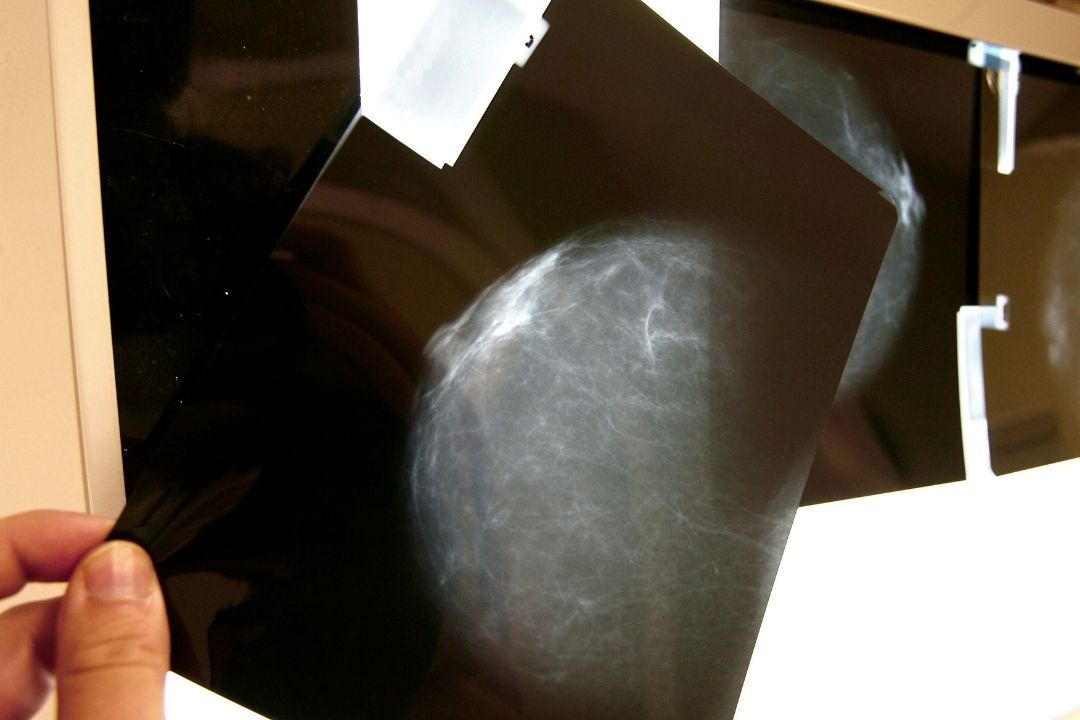

Contra el cáncer de mama, la autoexploración y detección oportuna marcan la diferencia. #OctubreRosa pic.twitter.com/ct0qNVQt5Z